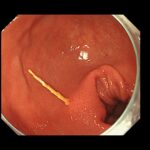

糞石による閉塞性大腸炎をきたしており、粘膜からの出血と腸に嵌頓する糞石を認めました。

糞石を内視鏡処置具で破砕していくと、何層にも重なり合う便の層を認めました。